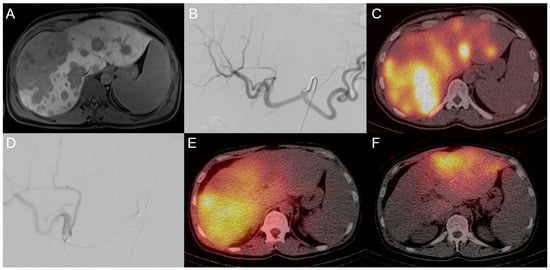

3.2. Transarterial Radioembolization (TARE)

- Gangi, A.; Shah, J.; Hatfield, N.; Smith, J.; Sweeney, J.; Choi, J.; El-Haddad, G.; Biebel, B.; Parikh, N.; Arslan, B.; et al. Intrahepatic Cholangiocarcinoma Treated with Transarterial Yttrium-90 Glass Microsphere Radioembolization: Results of a Single Institution Retrospective Study. J. Vasc. Interv. Radiol. 2018, 29, 1101–1108. [Google Scholar] [CrossRef]

- Hoffmann, R.T.; Paprottka, P.M.; Schon, A.; Bamberg, F.; Haug, A.; Durr, E.M.; Rauch, B.; Trumm, C.T.; Jakobs, T.F.; Helmberger, T.K.; et al. Transarterial hepatic yttrium-90 radioembolization in patients with unresectable intrahepatic cholangiocarcinoma: Factors associated with prolonged survival. Cardiovasc. Intervent Radiol. 2012, 35, 105–116. [Google Scholar] [CrossRef]